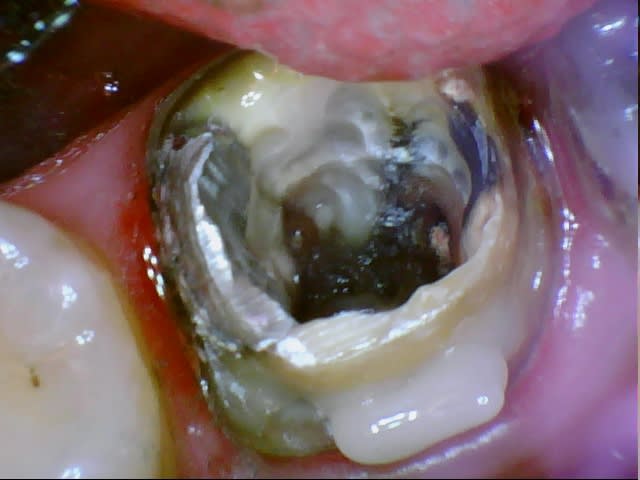

Quoique je me demande si le Vertise tiendrait pour l'application de boudin d'accroche pour crampon, technique que je viens d'essayer.

Celui-ci s'est barré en fin de séance à la dépose du crampon en utilisant un adhésif auto-mordançant qui est supérieur en valeur adhésive au Vertise mais bon faut essayer.

Compo pour digue z4sbuc - Eugenol

Dg oto4if - Eugenol